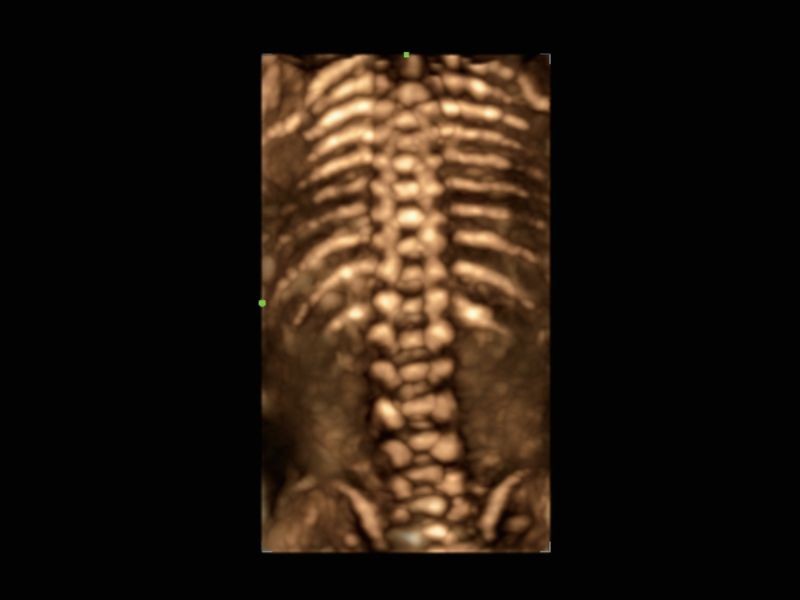

Cena Inteligente 3D

Solução obstétrica inteligente full-stack com tecnologia ZST⁺

OB inteligente

Medição automática de biometria fetal

Aviões inteligentes CNS

Reconhecimento automático e medição do sistema nervoso central fetal